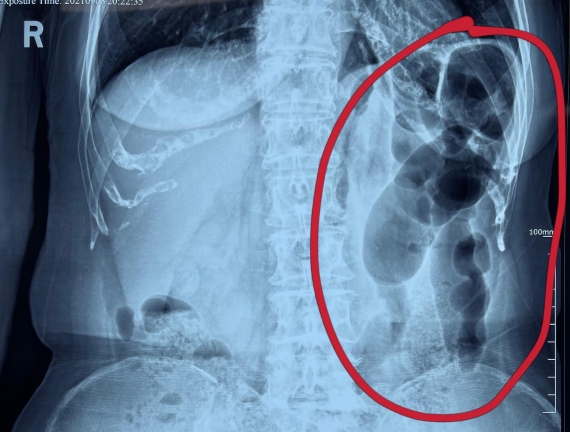

據(jù)省醫(yī)院消化病院消化二科姜子曄醫(yī)生介紹,韓大娘今年已經(jīng)73歲,家住哈爾濱市,一周前開(kāi)始腹脹腹痛,有較為明顯的左側(cè)腹部疼痛,疼痛劇烈時(shí)會(huì)出現(xiàn)左側(cè)腹部鼓包情況,排氣排便后有所好轉(zhuǎn)。韓大娘家人見(jiàn)狀將其送到了黑龍江省醫(yī)院,門(mén)診檢查腹部平片提示為左側(cè)腹部積氣,口服全消化動(dòng)力藥及通便治療后腹痛腹脹有所緩解,入院前再次突發(fā)左側(cè)腹痛加重伴有明顯腹脹,急診隨后以“腹痛腹脹原因待查”將韓大娘收入到消化病院消化二科。

姜子曄醫(yī)生熱情接待了韓大娘,為其進(jìn)行了仔細(xì)查體,除了左側(cè)腹部壓痛并未見(jiàn)明顯異常,對(duì)癥給予灌腸后,韓大娘的腹脹有所緩解,第二天姜子曄醫(yī)生為韓女士進(jìn)行了胃腸鏡檢查,也未見(jiàn)明顯異常。但此時(shí)韓大娘腹部平片結(jié)腸腸管擴(kuò)張仍然很嚴(yán)重,腹痛腹痛也沒(méi)緩解,到底什么原因呢?消化二科主任陸以霞在查房時(shí)建議繼續(xù)給予韓大娘口服全消化動(dòng)力藥,必要時(shí)灌腸治療,同時(shí)陸以霞主任在追問(wèn)病史查體時(shí)發(fā)現(xiàn)韓大娘左下腹紅色皮疹和小水泡,反復(fù)抓撓腹部皮膚部分已結(jié)痂,高度懷疑為帶狀皰疹。